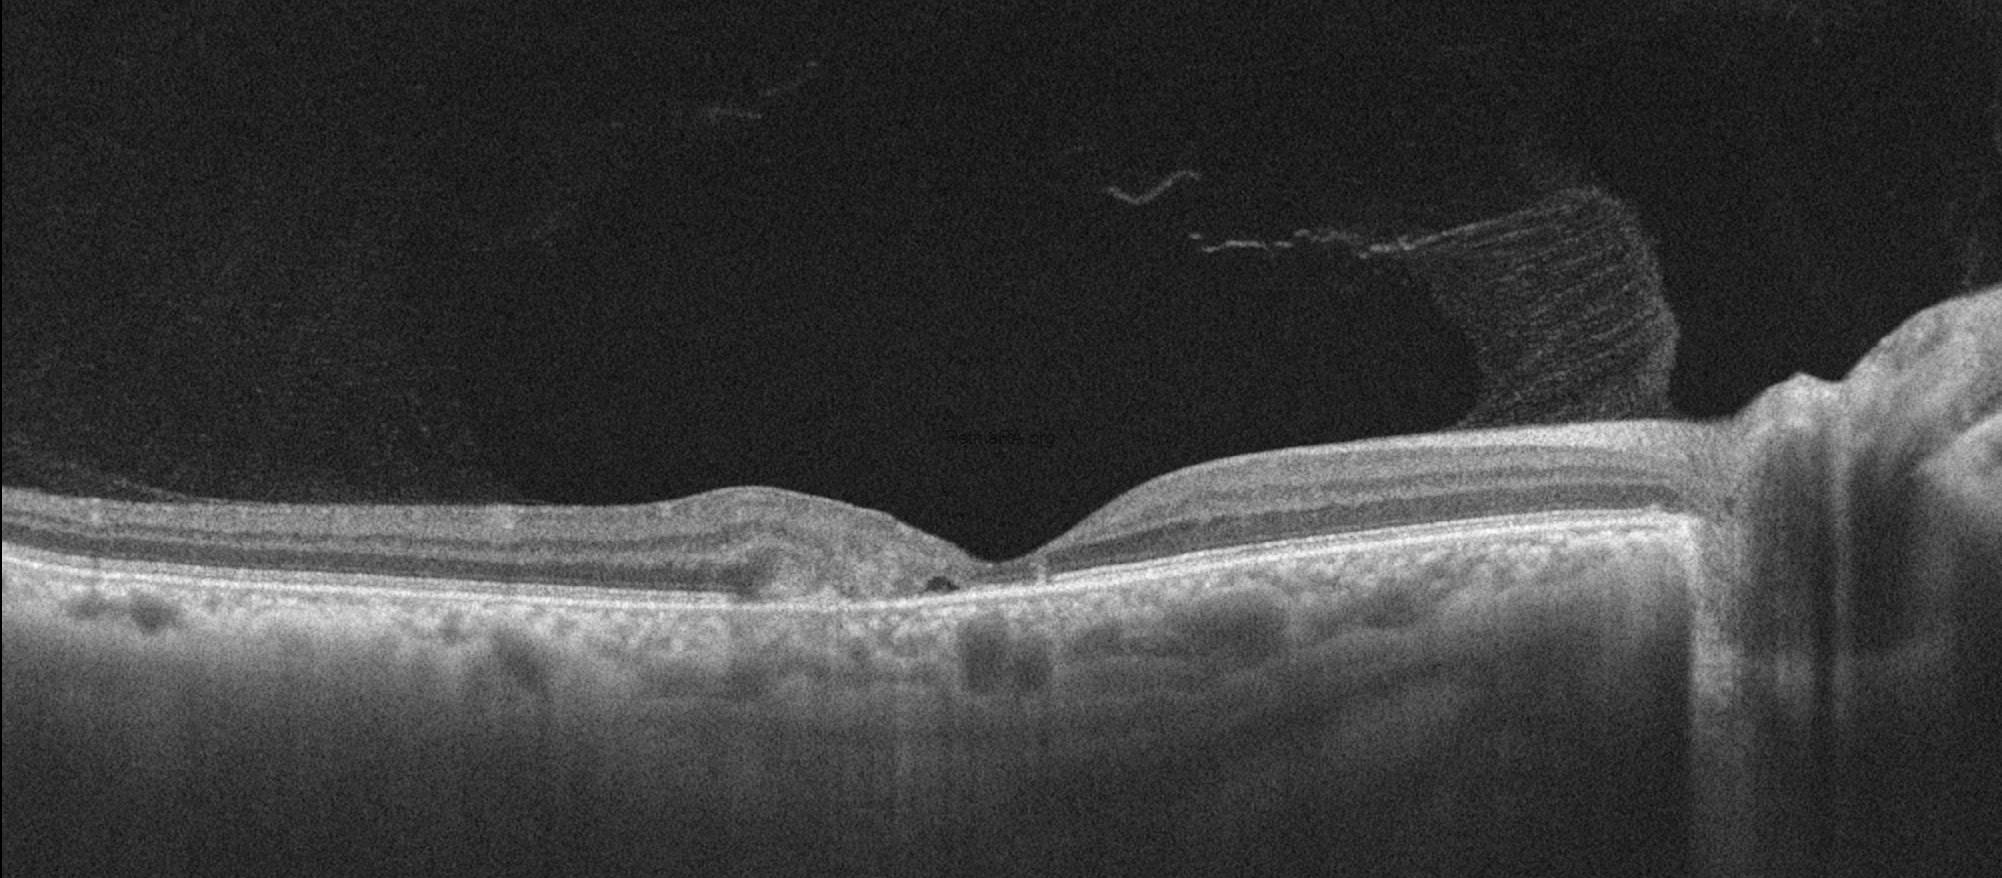

Optical coherence tomography (OCT) demonstrated characteristic parafoveal structural alterations, choroidal neovascularization in both eyes, and Henle fiber layer hemorrhage in the left eye. Early findings include inner and outer retinal cavitations, particularly involving the inner nuclear and outer plexiform layers, often without significant retinal thickening. Disruption and attenuation of the ellipsoid zone are observed in the temporal parafoveal region, reflecting photoreceptor damage. Thinning of the neurosensory retina and loss of normal foveal contour become evident. In the neovascular stage, OCT reveals subretinal hyperreflective material consistent with choroidal neovascularization, frequently accompanied by subretinal fluid, intraretinal cystic changes, and focal retinal thickening.

The patient’s imaging findings after three doses of anti-VEGF therapy are shown below. Visual acuity impoves after treatment to 0.5/0.4.Crystalline deposits are more prominent on color photography of the right eye after anti-VEGF treatment.

After the patient is treated with anti-VEGF injection, disorganization or intraretinal fluid and subretinal exudative fluid findings are resolved and the patient’s acuity returns to baseline.